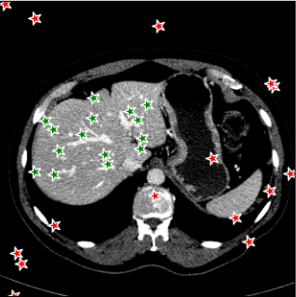

Points are the most fundamental interactions in semi-automatic annotation tools, but also most unpredictable. To train a new point-based prompt tailored to a specific annotation task, a stochastic process is employed wherein points are randomly sampled from the interval of within both the background and foreground regions of each annotated slice during every iteration of the training process. In this work, three distinct point selection schemes has also been investigated, namely ‘uniform’, ‘center’ and ‘boundary’. An example is illustrated in Fig. 5. In the case of uniform sampling, points are random selected with uniform distribution within the mask region. For center sampling, we primarily selected the points at the central location within the target region, by applying a distance transform. Conversely, the boundary sampling mainly selects the point near the boundary.

For 3D dataset, the SAM model will be initially trained on several randomly selected annotated slices, and then tested on the remaining slices. For 2D dataset, such as Kidney-US and Nuclear-Hist, the SAM model will be initially trained on several randomly selected cases, and test on other cases. We randomly sampled points from both foreground and background regions to train the new prompt. Each case will be trained and tested, individually. Figure 7 demonstrated the performance of the point-based SAM model. As the figure shows, single point on the target has shown remarkable segmentation performances using SAM even with only 2 annotated slices for the prompt training, compared to the original SAM model. Segmentation results of Kidney-CT are visualized in Figure 8. Segmentation results of one test slice is shown to demonstrate the significant improvement of SAM . Comparison results with other state-of-the-art segmentation results are shown in Table 2 including both fully-supervised (such as nnUNet, UNetr), fine-tune based SAM segmentation method (such as MedSAM, MSA).